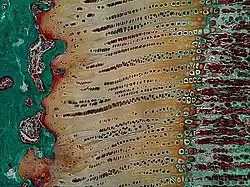

Masson Goldner trichrome stain of growth plate in a rabbit tibia.

Masson Goldner trichrome stain of growth plate in a rabbit tibia. -